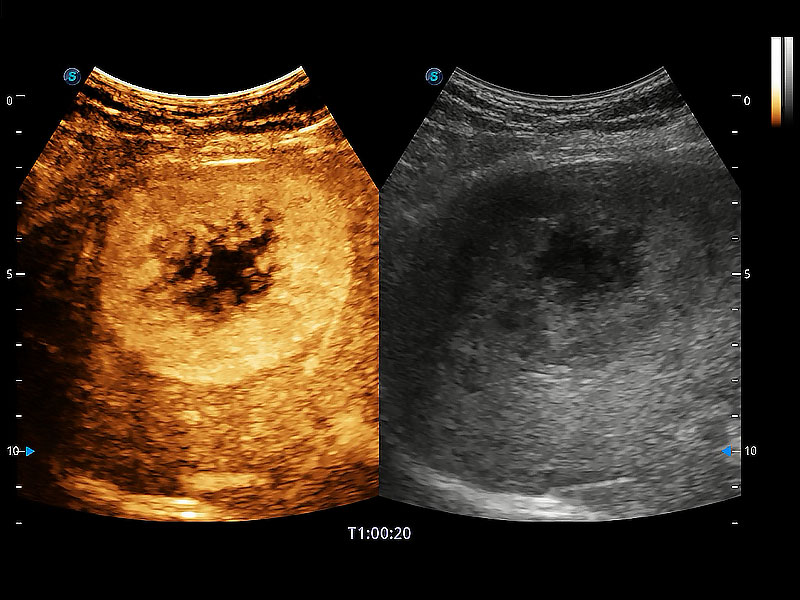

(犬)肝脏

(犬)肾脏显微血流